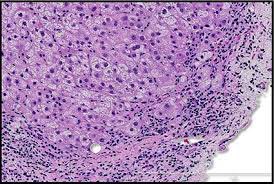

والمختبر المسؤول للتأكد من سلامة العضو هو histopathology lab عن طريق اخذ خزعة???‍⚕️